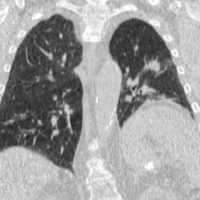

Four-dimensional computed tomography (4DCT) is a type of CT scanning which records multiple images over time. It allows playback of the scan as a video, so that physiological processes can be observed and internal movement can be tracked. The name is derived from the addition of time (as the fourth dimension) to traditional 3D computed tomography. Alternatively, the phase of a particular process, such as respiration, may be considered the fourth dimension.[1]

To minimise physical movements of the patient, some sort of immobilisation is typically used. To overcome physiological motion, such as breathing, 4DCT acquires images at a range of times and positions, allowing the extent of motion to be visualised (e.g. from maximum inspiration to maximum exhalation). The treatment plan can then be designed with a knowledge of the full range of possible positions of important organs, and the tumour (target) itself.[8]